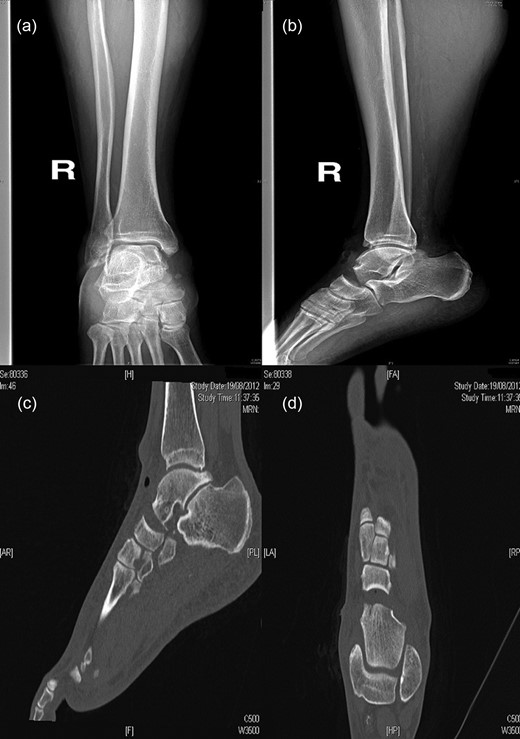

In August 2012, a 49-year-old-man presented to our hospital with a traumatic forefoot subamputation after a work accident. The trauma caused a lacerated wound in correspondence of the dorsal surface of the right foot. Radiographs and computed tomography (CT) examination confirmed the diagnosis of the loss of talus head during the trauma (Fig. 1).

AP (a) and lateral (b) radiographs and CT images (c, d) confirm the diagnosis of the loss of talus head during the trauma.